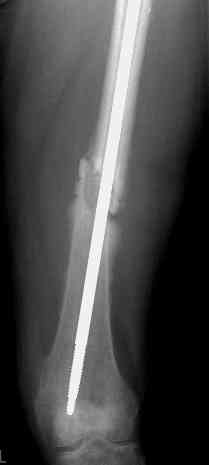

Уважаемые коллеги!На прилагаемых снимках - состояние после оперативного вмешательства (открытый перелом левого бедра в средней трети):

МОС, стержень нефиксированный. С момента операции прошло 8 месКак по Вашему мнению происходит консолидация? Допустимо ли смещение или необходима повторная операция по выравниванию конечности? Если да, какой метод рекомендуете (фиксированный стержень, пластина)?Буду благодарен за оперативный ответ.

Вы не пишете, есть ли сейчас болезненные проявления, и какие. Как пациент ходит. Какова функция колена. Ось выглядит приемлемо. Рентгенологически на сращение непохоже. Если есть клиника несращения (боль, хромота), то лучший выбор - закрыто рассверлить и перештифтовать блокированным гвоздем. Желательно определиться поточнее, нет ли проблемы с длиной , чтобы попутно и ее решить. И не создать. Ну и прежде всего исключить инфекцию. Если это инфицицированное несращение, план надо другой.

При таком диаметре штифта не удивительно, что перелом не сросся (кстати, какой диаметр и что за модификация штифта?).

Допустимо ли смещение...

В этой проекции угловое смещение градусов 15-20 - многовато будет. Есть ли укорочение?